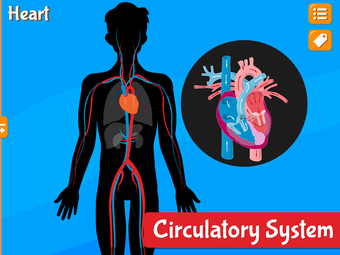

Anatomix es un juego de aprendizaje de anatomía humana que te enseñará a identificar todos los huesos del cuerpo humano y te permitirá explorar cada sistema en detalle. A medida que explores cada sistema, podrás identificar todos los huesos, músculos y otras estructuras.

Además de eso, podrás utilizar los diferentes huesos para identificar los diferentes sistemas.

La aplicación también te ayudará a identificar los diferentes huesos de tu propio cuerpo y te permitirá explorar cada sistema en detalle.